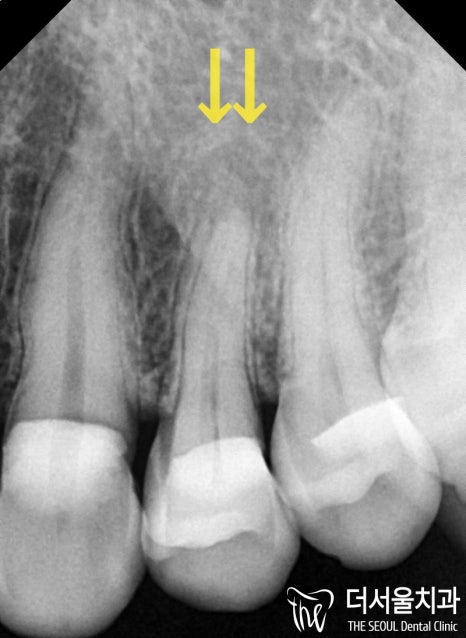

검진을 진행하여 확인해 보니

뿌리에 염증이 잡힌

치근단염이 생긴 것으로 확인되었는데요.

이전에 씌워놓은 골드 크라운 하방으로

이차적인 문제가 발생하여

이렇게 뿌리 끝까지 감염이 된 것으로

추측을 할 수 있었습니다.